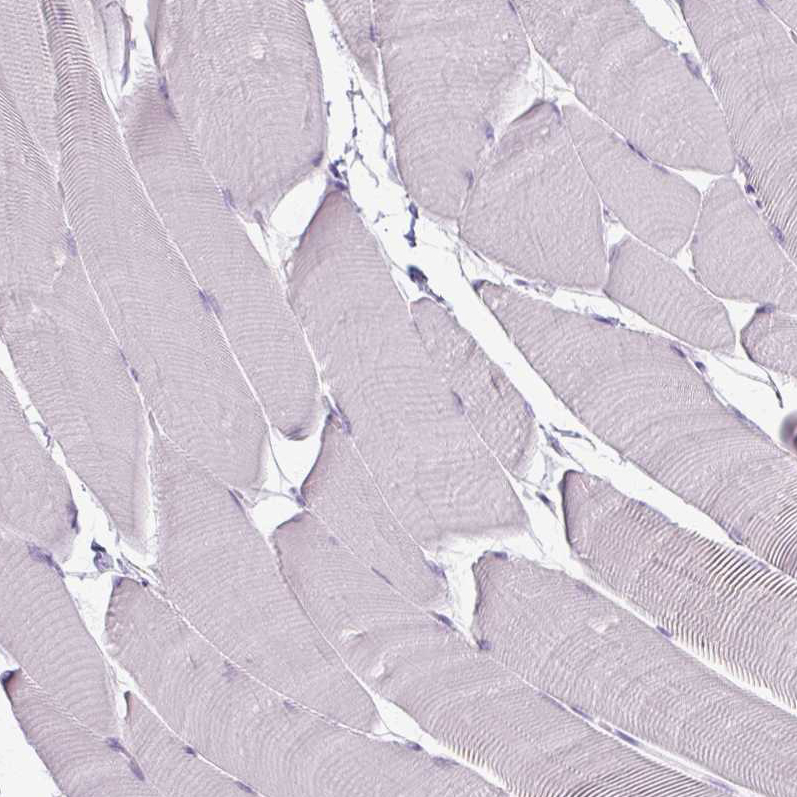

Immunohistochemistry analysis in human tonsil and skeletal muscle tissues using AMAb90519 antibody. Corresponding PTPRC RNA-seq data are presented for the same tissues.